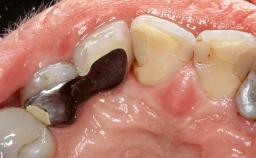

Treatment of Peri-Implantitis at a Zirconia Implant

Due to their promising clinical performance, zirconia implants have recently become popular alternatives to titanium implants, particularly for areas with high esthetic demands (Holländer and coworkers 2016; Roehling and coworkers 2016; Lorenz and coworkers 2019). However, regardless of the reported high survival and success rates, zirconia implants were affected by peri-implant diseases over the short observation period, suggesting the importance of treating peri-implant diseases at zirconia implants (Becker and coworkers 2017). In their case, Frank Schwarz and Ausra Ramanauskaite present 3-year results following mechanical debridement alongside Er:YAG laser monotherapy.